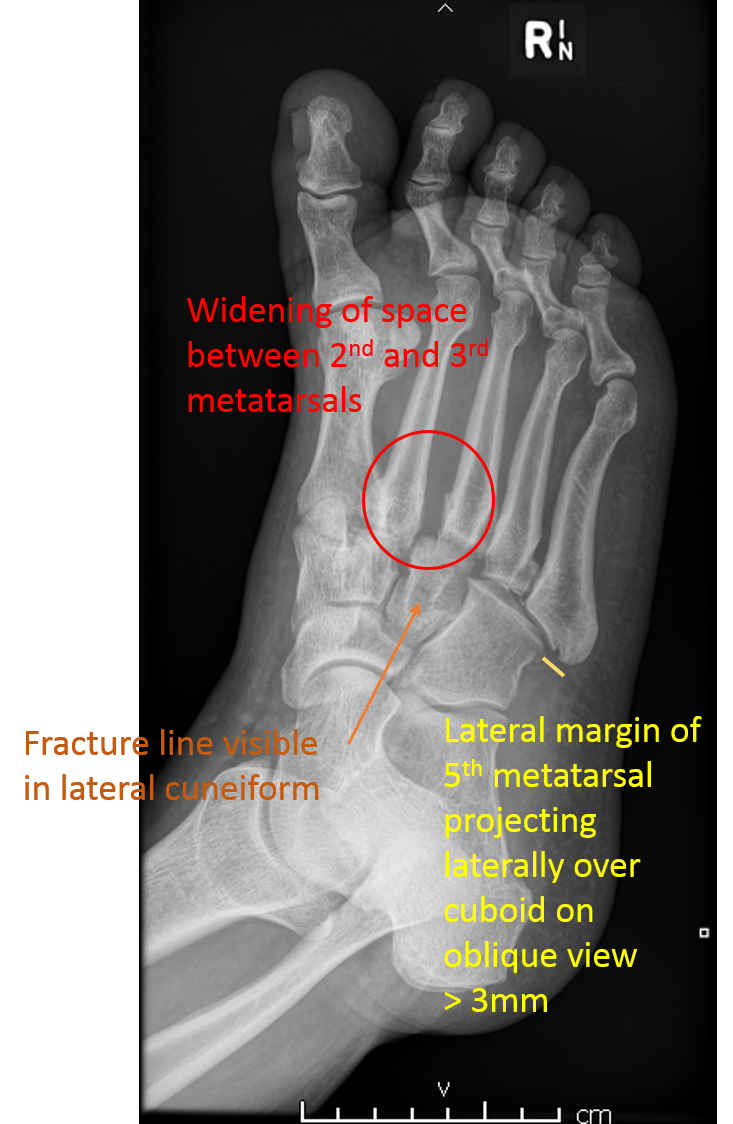

lisfranc损伤是常见的跗跖关节骨折和/脱位。

CASE M50 失步后从楼梯上摔下来 Case contributed by Dr Rozanne Visvalingam

骨折和LISFRANC间隙增宽的注解图像